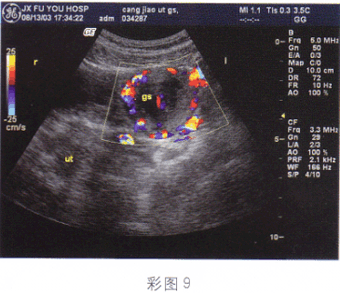

5.26歲,停經45天,陰道不規則出血4天,血HCG66μg/ml,結合超聲圖像,最可能的診斷為(彩圖9)

A.盆腔畸胎瘤

B.附件炎性包塊

C.子宮漿膜下肌瘤

D.異位妊娠

E.卵巢囊腺瘤

正確答案:D解題思路:附件區見囊實混合性光團,邊界尚清晰,子宮腔內有分離,患者有停經,不規則陰道出血,且血HCG增高。